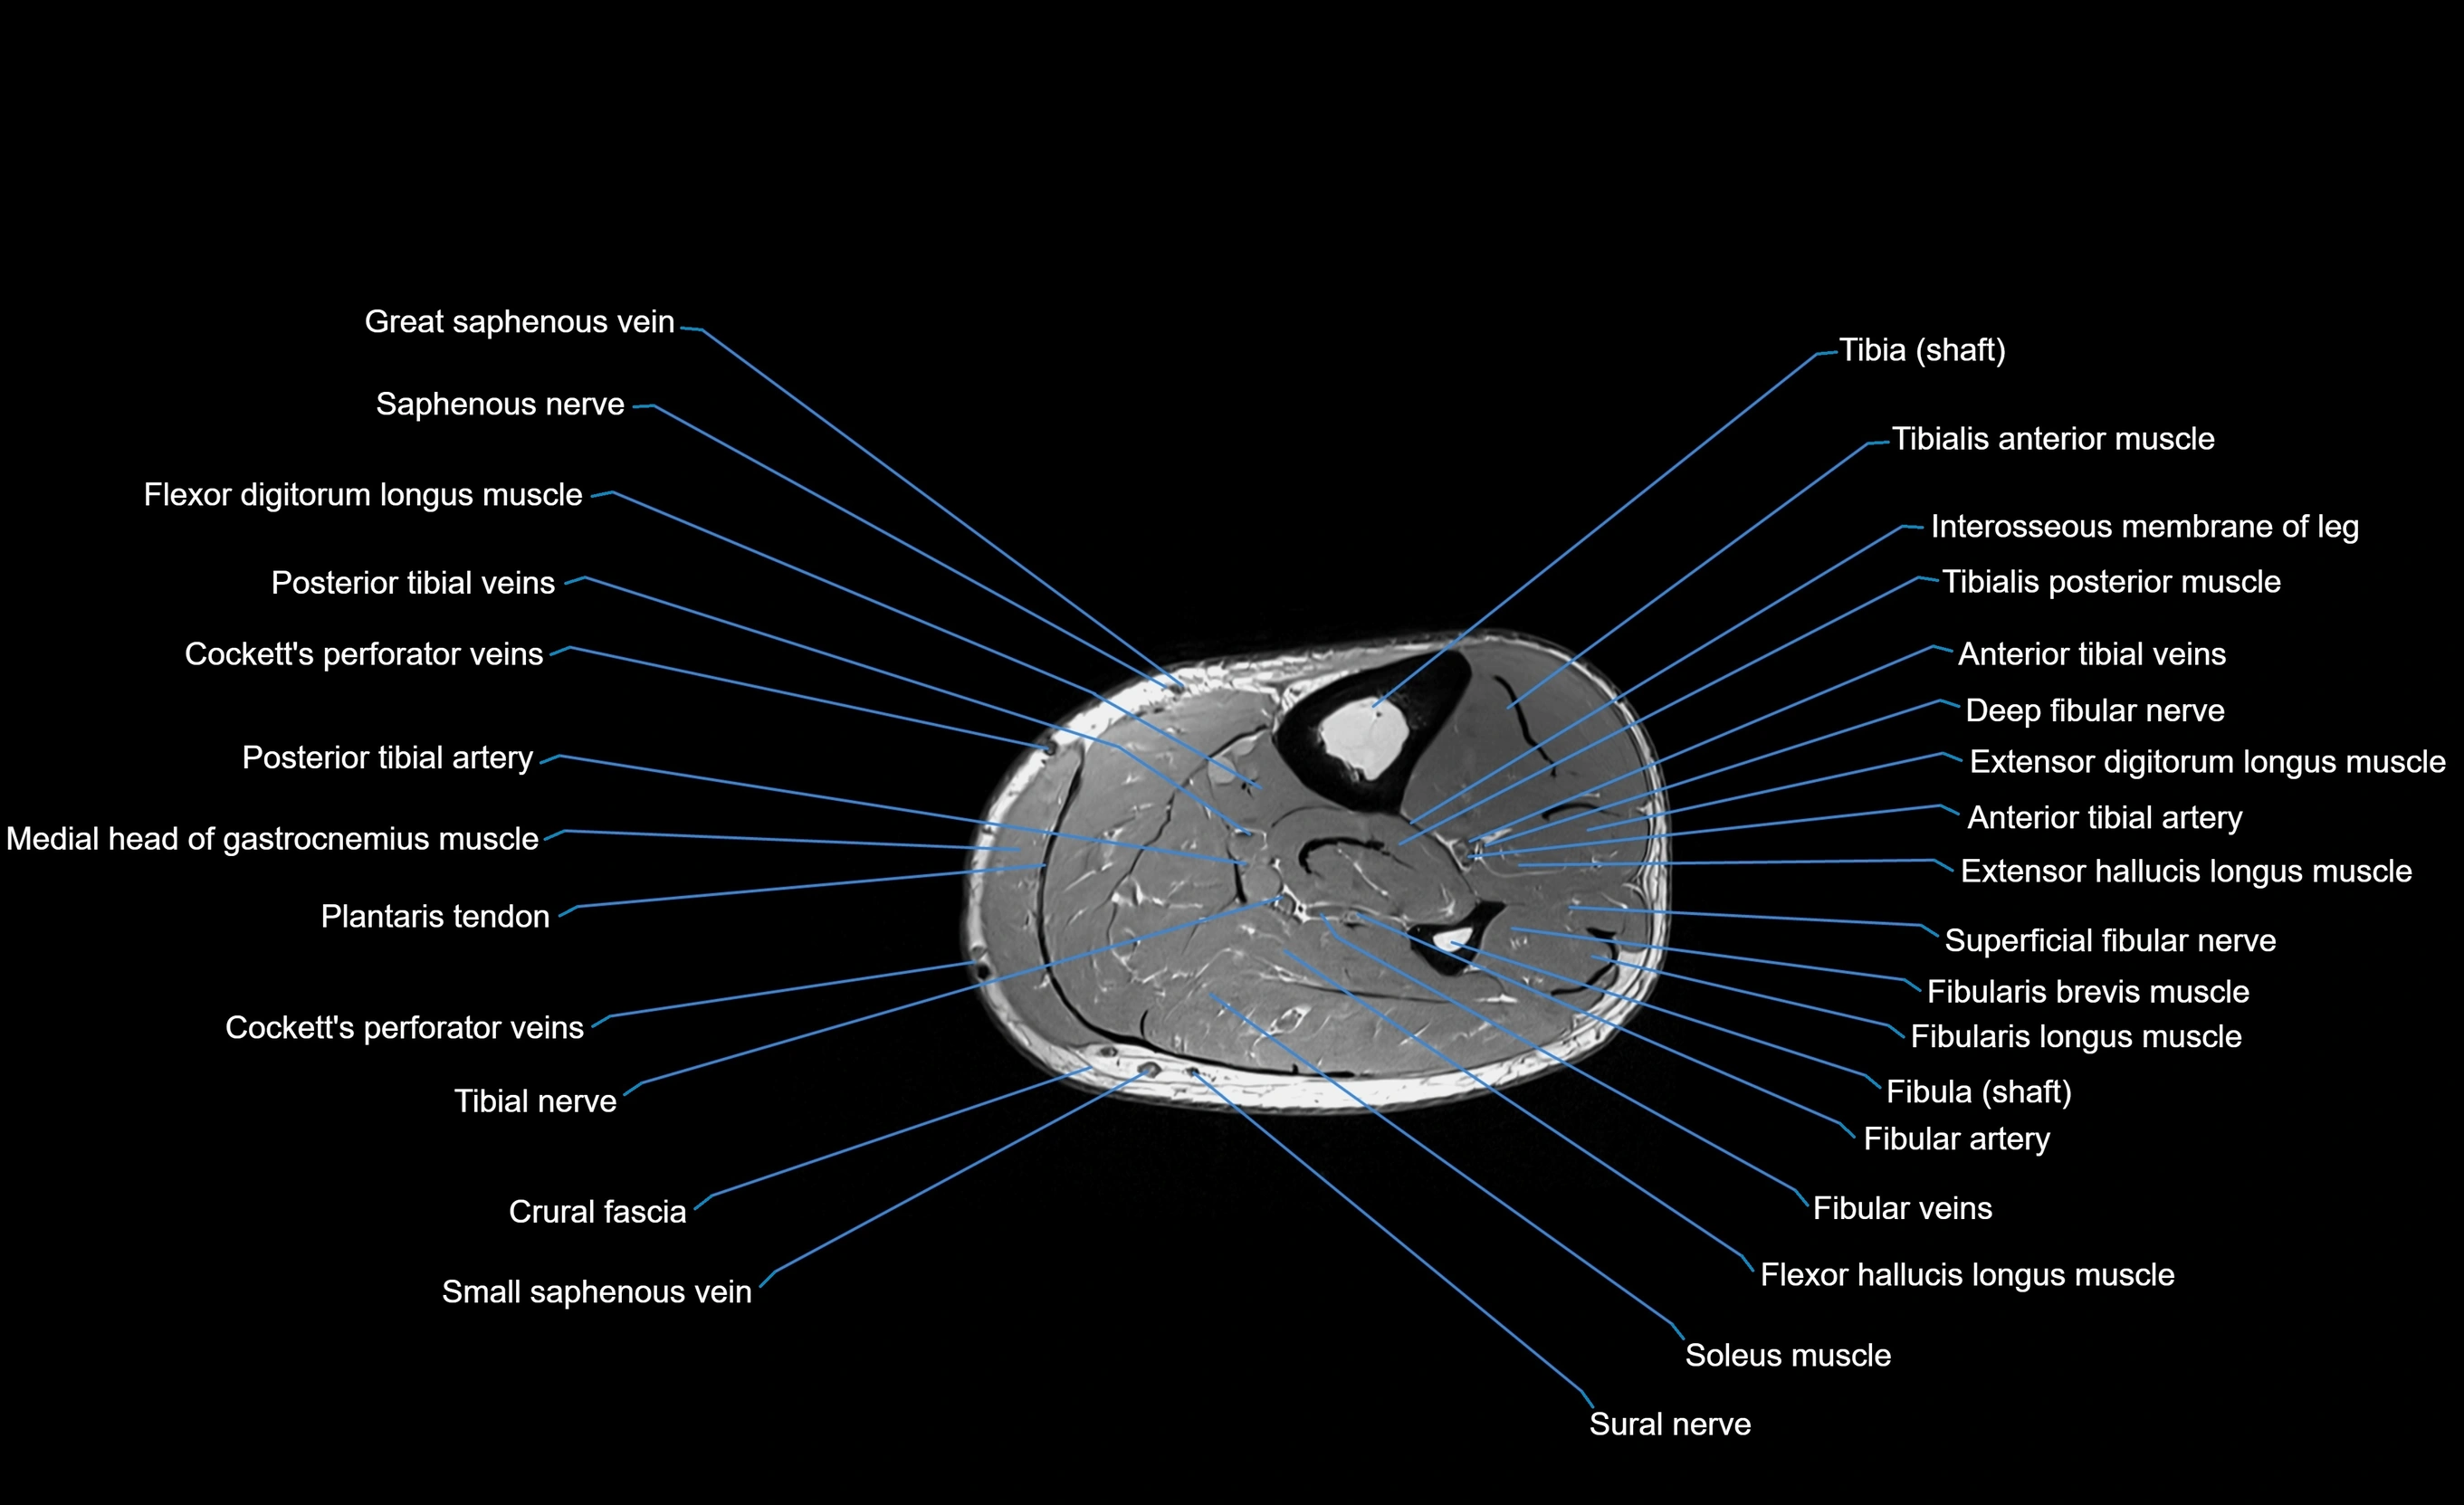

MRI image